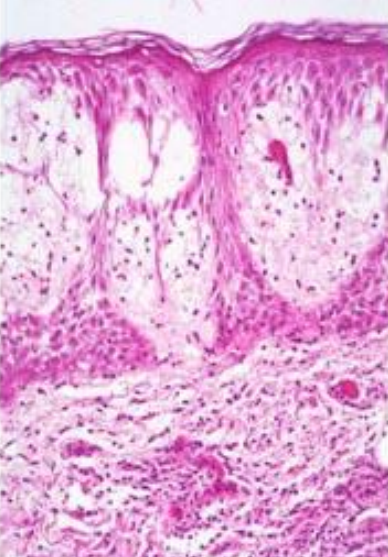

What do you expect to see histologically in a contact dermatitis response?

Intradermal blistering. The immune response causes spongiosis and lymphocyte infiltration.